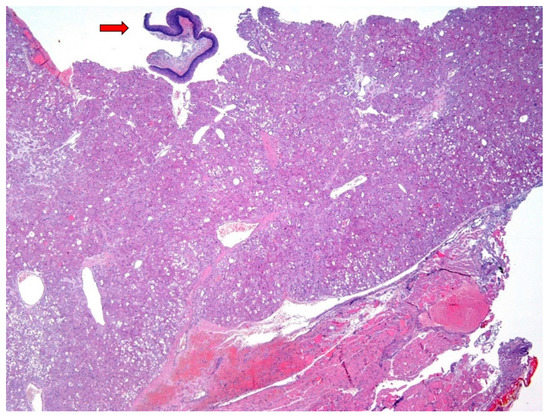

Figure 2. An excisional biopsy was performed. On gross exam, the lesion had a hemorrhagic appearance. Histological examination revealed a highly cellular tumor (upper part of the Figure), involving the subepithelial connective tissue, with extensive superficial de-epithelization (arrow: residual squamous epithelium of the vocal cord). The lesion was unencapsulated and mainly well-delimited from the underlying striated muscle layer (lower part of the Figure), with pushing growth borders; however, the partial fragmentation of the material did not allow a complete definition of the tumor growth front. The surgical margins were involved, while biopsies of the bilateral false vocal cords were unaffected (Hematoxylin and Eosin, 4×; previously unpublished, original photo).